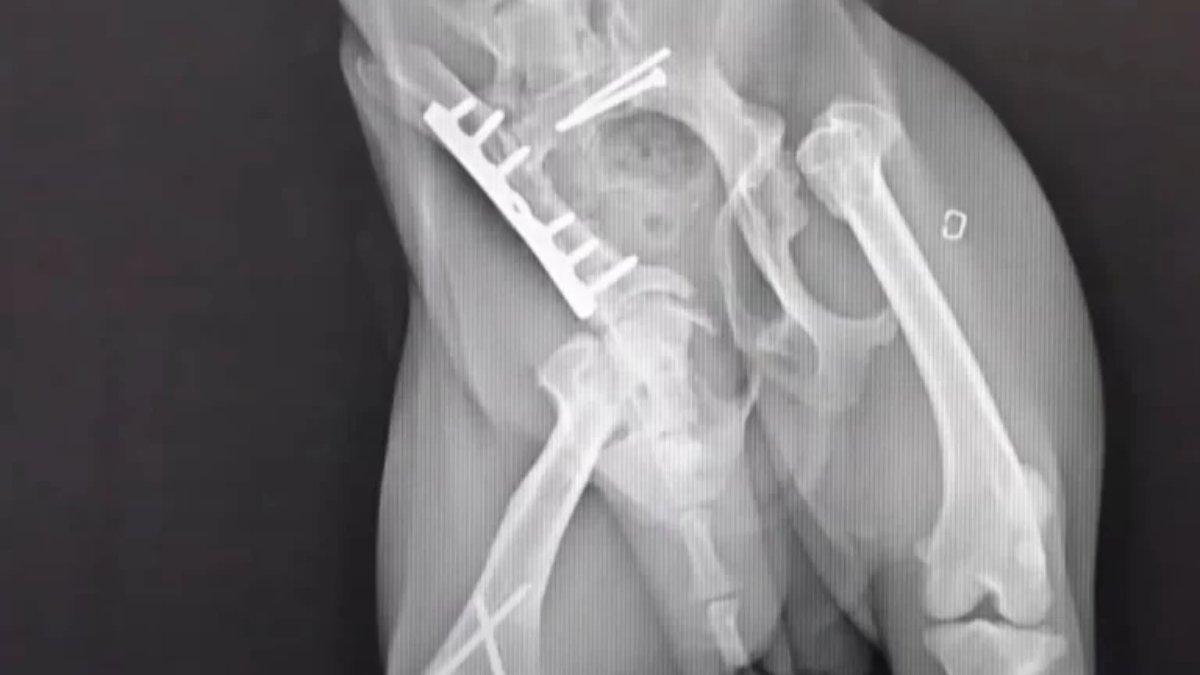

Hosun terluka cukup parah hingga kaki belakang patah dan hampir tak bisa berjalan.

Setelah didiagnosa dokter, Hosun ternyata mengalami beberapa patah tulang panggul dan kaki belakang.

Setelah kisahnya banyak diliput media, seorang ahli bedah hewan menawarkan jasanya untuk mengoperasi Hosun.

Kemudian Hosun menjalani pemulihan hingga akhirnya semua prosedur berhasil dijalani.

Hosun pun kini bisa menggunakan keempat kakinya untuk berjalan dengan normal.